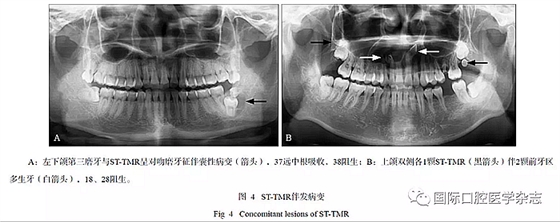

伴發(fā)病變包括:含牙囊腫2例[2例下頜的STTMR與第三磨牙牙冠相對(duì)呈對(duì)吻磨牙征(kiss molars)]、前牙區(qū)多生牙3例(其中1例上頜前牙區(qū)2顆多生牙,右側(cè)伴囊性病變經(jīng)術(shù)后病理證實(shí)為牙源性囊腫伴感染,病理號(hào)Z-201702789)、鄰牙阻生28例、鄰牙根吸收5例(圖4)、冠周骨質(zhì)改變13例、鄰牙齲病2例、多個(gè)牙阻生1例。